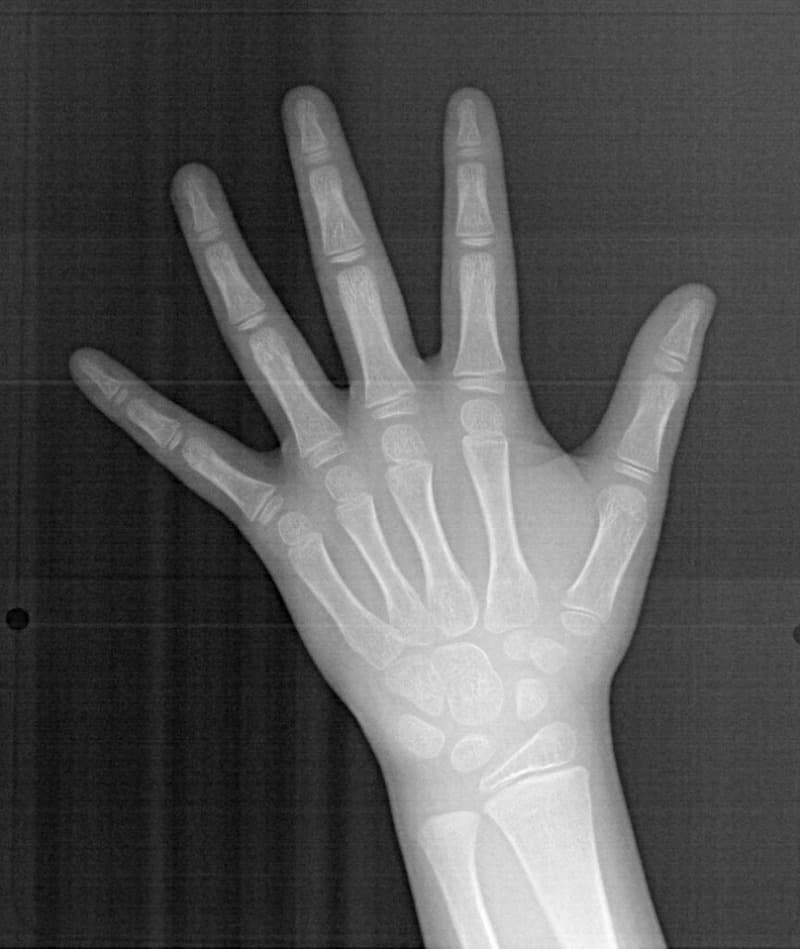

FX(フェイシャルアキシス)は85度なので東洋人の平均値に近く、下顎が前方に過剰成長するリスクは強くはありません。

しかしやはり上顎は劣成長で、下顎が優位な状態ではあります。

骨年齢は実年齢よりも低めなので、今後下顎の旺盛な成長が見込まれます。

検査時のレントゲン分析では、上下顎の関係は、上顎の劣成長があり下顎前突傾向という値がでておりましたが、前歯ジャンプ後はフェイスマスクの効果もあり、上下顎の関係は正常化しています。

上顎が若干優位になっていますので、今後の下顎の成長のための貯金になっているくらいです。